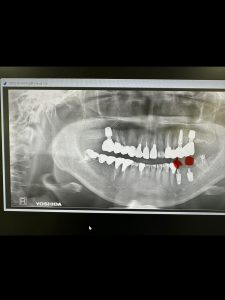

今朝は、インプラントオペ

これで5本目、安定も良く6w後には型取り、仮歯かな